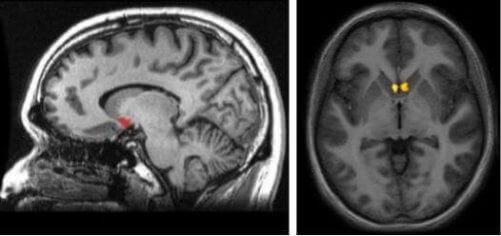

Elke hersenhelft heeft een nucleus accumbens. Samen vormen ze je complexe beloningssysteem. Dankzij dit deel van de hersenen kun je genot ervaren, kun je nieuwe kennis opdoen en vind je de motivatie die je nodig hebt voor je dagelijkse leven.

Nu vraag je je misschien af waar dit hersengebied zich bevindt. Visualiseer het subcorticale gebied (onder de cortex) op het verbindingspunt tussen de caudate nucleus, het putamen en het septum om het te conceptualiseren.

Elk van de hersenhelften heeft zijn eigen nucleus accumbens. Op die manier bereikt het door dopamine beheerde beloningssysteem elk deel van de hersenen. Deze structuur maakt ook deel uit van de basale ganglia. Als zodanig is een van de belangrijkste kenmerken van de nucleus accumbens de mate waarin het verbonden is met andere delen van de hersenen.